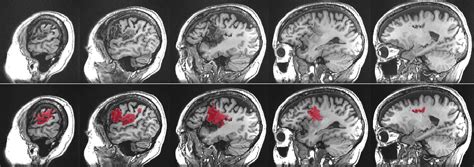

Let’s talk about causes of aphasia . Understanding what triggers this language disorder is super important for prevention and treatment strategies. The primary cause of aphasia is damage to the language-dominant areas of the brain. For most people, the left hemisphere of the brain is responsible for language functions. When these areas are injured, aphasia can result. The most common culprit, as we’ve touched upon, is a stroke . Strokes occur when blood supply to a part of the brain is interrupted, either by a blockage (ischemic stroke) or by bleeding (hemorrhagic stroke). This lack of blood flow deprives brain cells of oxygen, causing them to die. Depending on which part of the brain is affected, language abilities can be severely impacted. Another significant cause is Traumatic Brain Injury (TBI) . TBIs can happen from blows to the head, falls, or accidents. The widespread nature of the damage in a TBI can affect various brain functions, including language. Brain tumors can also lead to aphasia . Whether the tumor is malignant or benign, its growth can press on or invade brain tissue, disrupting normal function, including language processing. Brain infections , such as encephalitis (inflammation of the brain), can also cause damage to language areas. Lastly, neurodegenerative diseases are a cause, particularly Primary Progressive Aphasia (PPA). PPA is a group of brain disorders caused by specific types of dementia that target the brain’s language networks. Unlike other causes where aphasia might appear suddenly, PPA is typically a gradual decline. Each of these causes of aphasia presents unique challenges in terms of diagnosis, treatment, and prognosis. Knowing the cause helps medical professionals tailor the approach to managing aphasia , aiming to restore as much language function as possible and improve the quality of life for those affected. It’s a complex puzzle, and identifying the root cause is a critical piece.

Now, let’s get into the nitty-gritty: the types of aphasia . Because aphasia is caused by damage to different parts of the brain, it doesn’t just show up as one single problem. Instead, it’s classified into various types, each with its own set of characteristics. This classification helps speech-language pathologists (SLPs) understand the specific challenges a person is facing and develop targeted therapy. The two main categories are often fluent aphasia and non-fluent aphasia , with further subtypes within each.

Fluent Aphasia